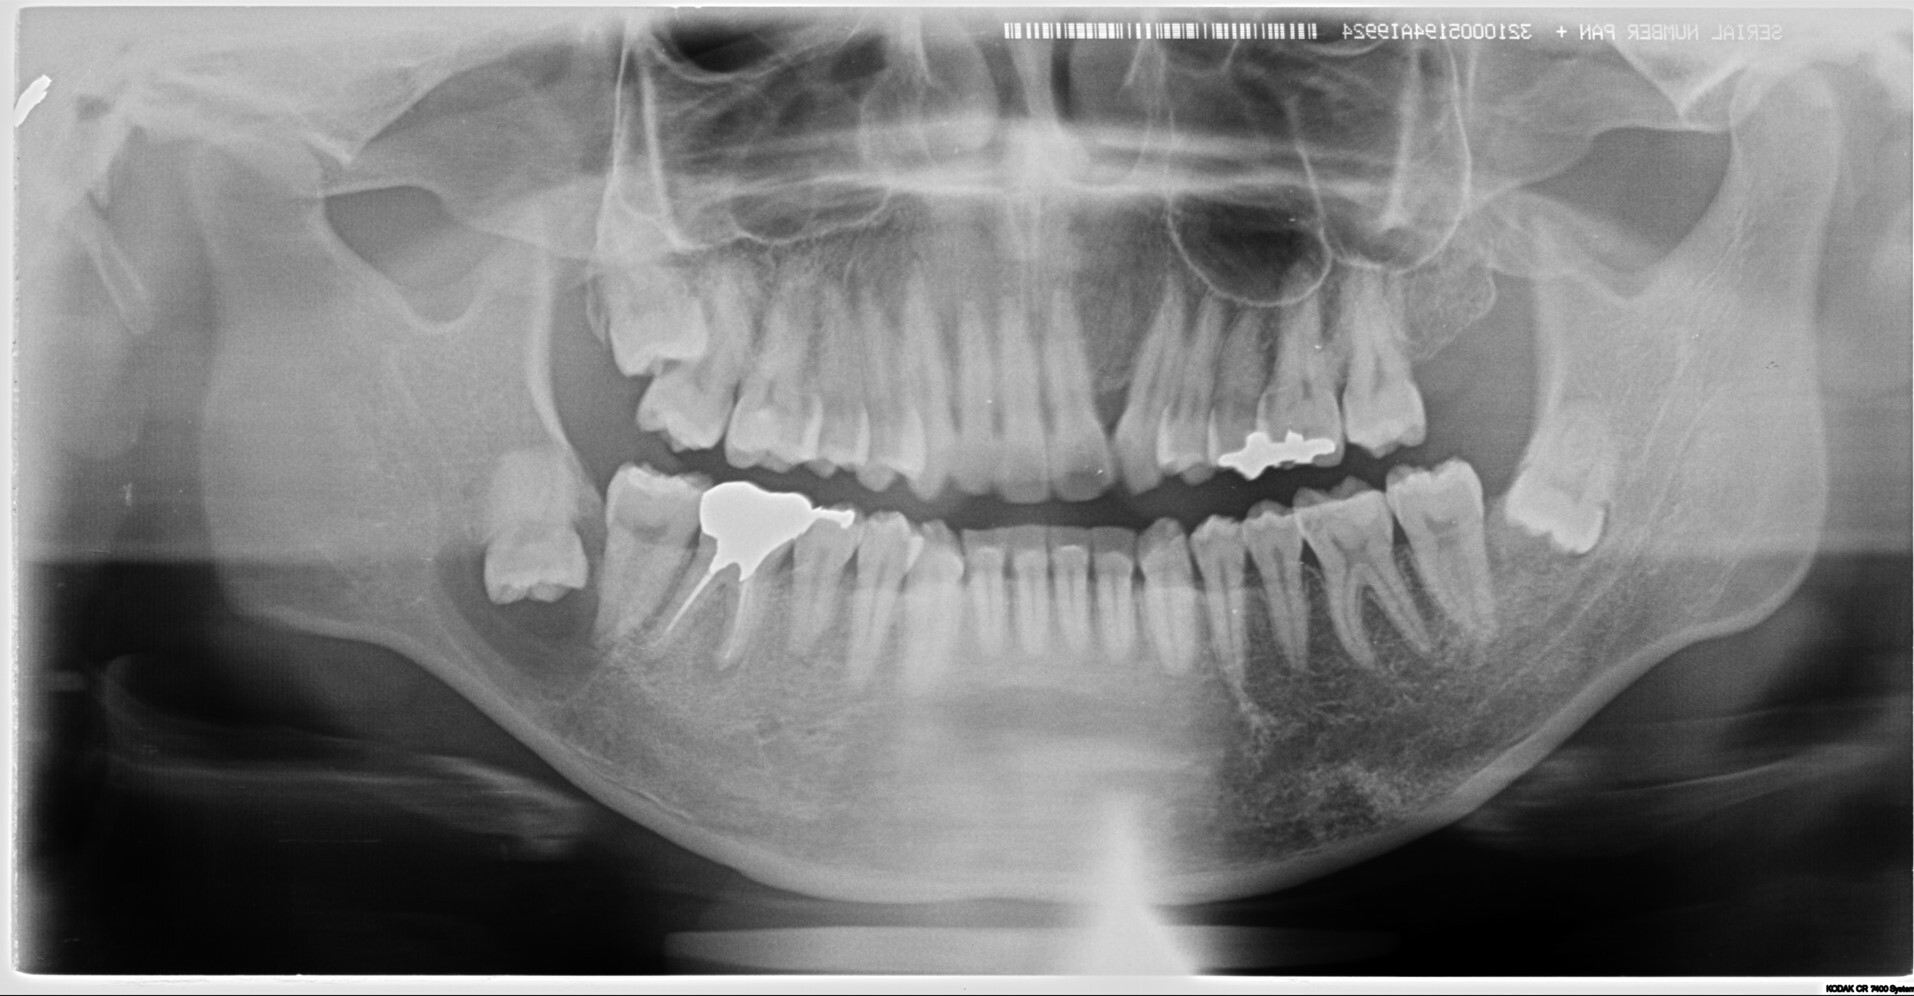

某大学病院で全身麻酔での嚢胞摘出及び右下7番の抜歯を予定されていた方の治療経過

<親知らずなどの抜歯に関して>

多くの方が経過観察になっていることが多いのが親知らずでしょう。一度腫れたりすると抜歯をしようかなと考えて歯科医院に行くケースもありますが。

完全に埋まっているケースは放置されることが多いです。(自覚症状がないため)

またそうした難抜歯は通常開業医では行わないケースが多いです。

しかし当クリニックではそうした難抜歯を積極的に行っております。

理由は簡単で症状が「歯列の乱れ」「歯周病の悪化」「口臭の原因」「手前の歯を虫歯にしてしまう」からです。

完全に埋伏しているように見えても、抜歯した時には歯茎の中にあるにもかかわらず歯石まみれの汚い状態で抜歯できるケースはザラにあります。

ご本人が気が付かないだけで、埋まっている歯ぐきから膿が常に出ている方もたくさんいらっしゃいます。(特に40代以降の方に多い)

こうした方々は常に口臭がしたり、体調によって歯茎が腫れたりしています。

他の開業医で「大学病院などでの抜歯を勧められた」などの困難症例もご相談ください。

大学病院では全身麻酔などを行い抜歯するケースも多いですが。

麻酔科医としての見解からすれば、わざわざ全身麻酔を行い(呼吸を停止させ、挿管し人工呼吸で管理することです)抜歯を行うケースは相当のリスクを伴います。

可能な限り外科処置に関しては局所麻酔で抜歯を行う事が侵襲は少ないと考えます。

そのため原則局所麻酔下(部分だけの麻酔)での抜歯を行っております。

必要な症例に関しては大学病院等に紹介をいたします。